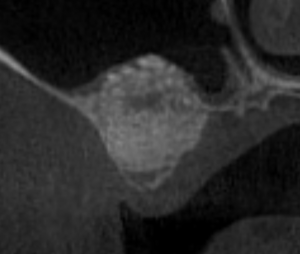

初診時(デンタル) 初診時(CT)

根管充填が不十分で、すき間もあり不良である